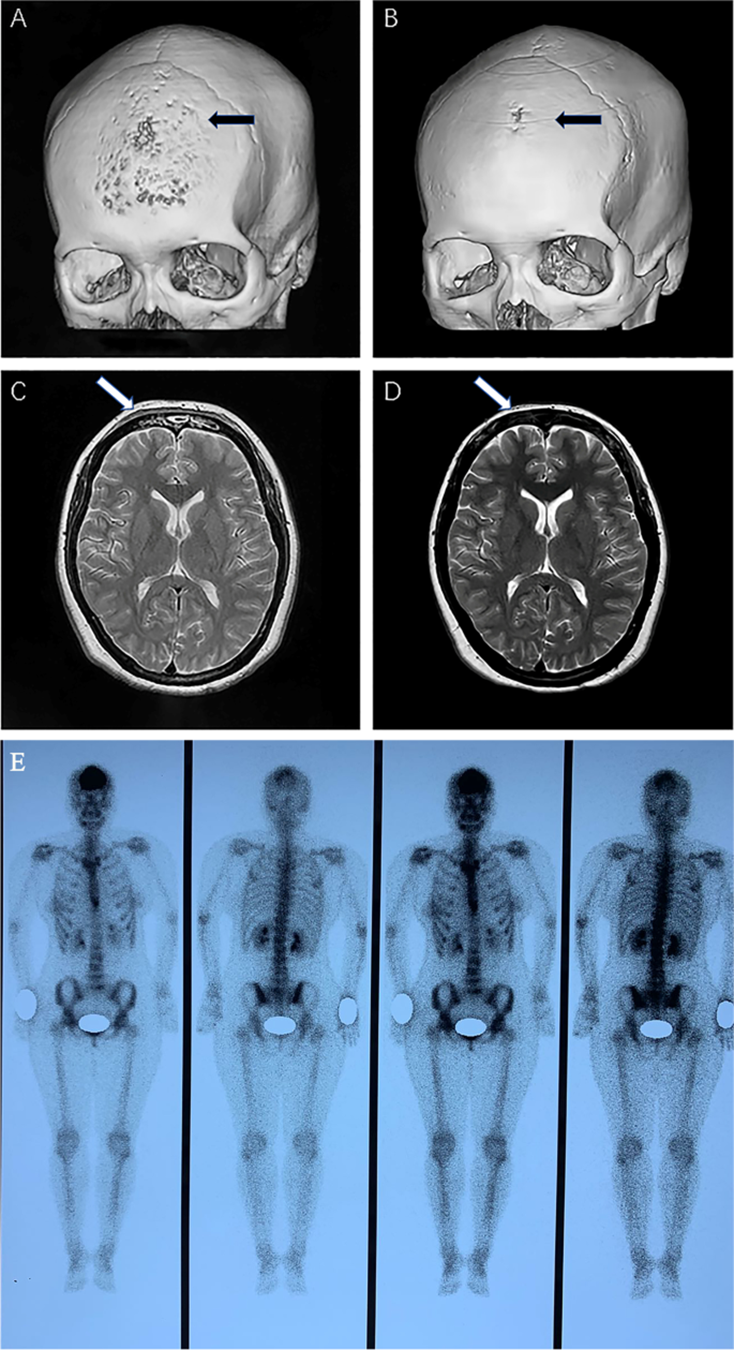

영상 진단: 특징적 징후와 감별 포인트

SAPHO 증후군은 임상 증상만으로는 감염성 골수염이나 골종양과 구별하기 어렵기 때문에 영상 의학적 검사가 진단의 핵심이 된다.1 다양한 영상 기법을 조합하여 질환의 활동성과 범위를 파악하는 것이 중요하다.10

골 스캔과 "Bull's Head" 징후

Technetium-99m을 이용한 골 신티그라피(Bone Scan)는 전신 골격의 침범 여부를 한눈에 파악할 수 있는 유용한 도구이다.10 특히 전흉벽의 흉쇄관절과 흉골 자루 부위에 강한 섭취 증가가 대칭적으로 나타나는 양상을 '황소 머리 징후(bull’s head sign)'라고 부르며, 이는 SAPHO 증후군을 시사하는 매우 특징적인 소견이다.10 비록 이 징후가 모든 환자에서 나타나는 것은 아니지만, 발견될 경우 진단적 가치가 매우 높다.10

자기공명영상(MRI)과 전산화단층촬영(CT)

MRI는 조기 병변을 발견하는 데 가장 민감한 검사이다.8 특히 지방 억제 T2 강조 영상이나 STIR 영상에서 관찰되는 골수 부종(bone marrow edema)은 활성도가 높은 골염을 나타낸다.8 또한 연부 조직의 염증과 관절 삼출액을 확인하는 데 탁월하며, 종양성 병변과의 감별을 위해 필수적이다.8

반면 CT는 뼈의 구조적 변화를 상세히 관찰하는 데 적합하다.8 과골화증으로 인한 피질의 비후, 골수강의 협소, 골 미란 및 경화의 정도를 정밀하게 평가할 수 있으며, 특히 전흉벽이나 하악골처럼 해부학적으로 복잡한 부위의 변화를 파악하는 데 유용하다.10